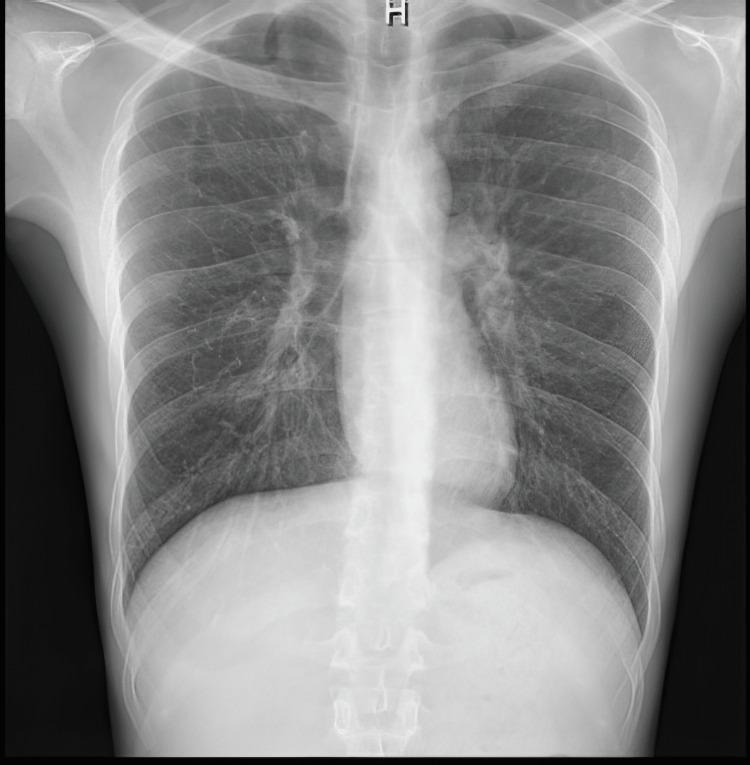

Peripheral neuropathy is a common manifestation of Eosinophilic Granulomatosis with Polyangiitis (EGPA), a rare autoimmune disorder caused by eosinophilic infiltration of multiple organs including the nervous system. Recent research has shown an association between myelin oligodendrocyte glycoprotein (MOG) antibodies and various neurologic conditions. We present a unique case of EGPA with positive MOG antibodies in the cerebrospinal fluid (CSF) in a patient presenting with peripheral neuropathy. We also highlight a few diagnostic dilemmas with EGPA and the importance of early diagnosis and appropriate treatment. Clinical, laboratory, radiological, and electrophysiologic findings are discussed.

周围神经病变是嗜酸性肉芽肿性多血管炎(EGPA)的常见表现,EGPA是一种罕见的自身免疫性疾病,由包括神经系统在内的多个器官嗜酸性粒细胞浸润引起。最近的研究表明,髓鞘少突胶质细胞糖蛋白(MOG)抗体与各种神经系统疾病之间存在关联。我们报告了1例周围神经病变患者脑脊液(CSF)中MOG抗体呈阳性的EGPA独特病例。我们还强调了EGPA的一些诊断难题以及早期诊断和适当治疗的重要性。文中讨论了临床、实验室、影像学和电生理检查结果。